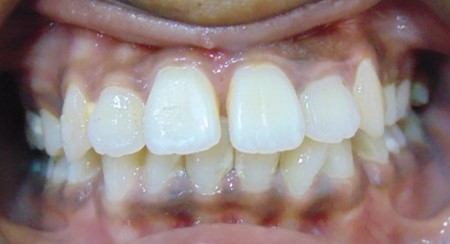

Akshay Jadhav, 30Y, Duration - 10Months

Before

After

Image 2